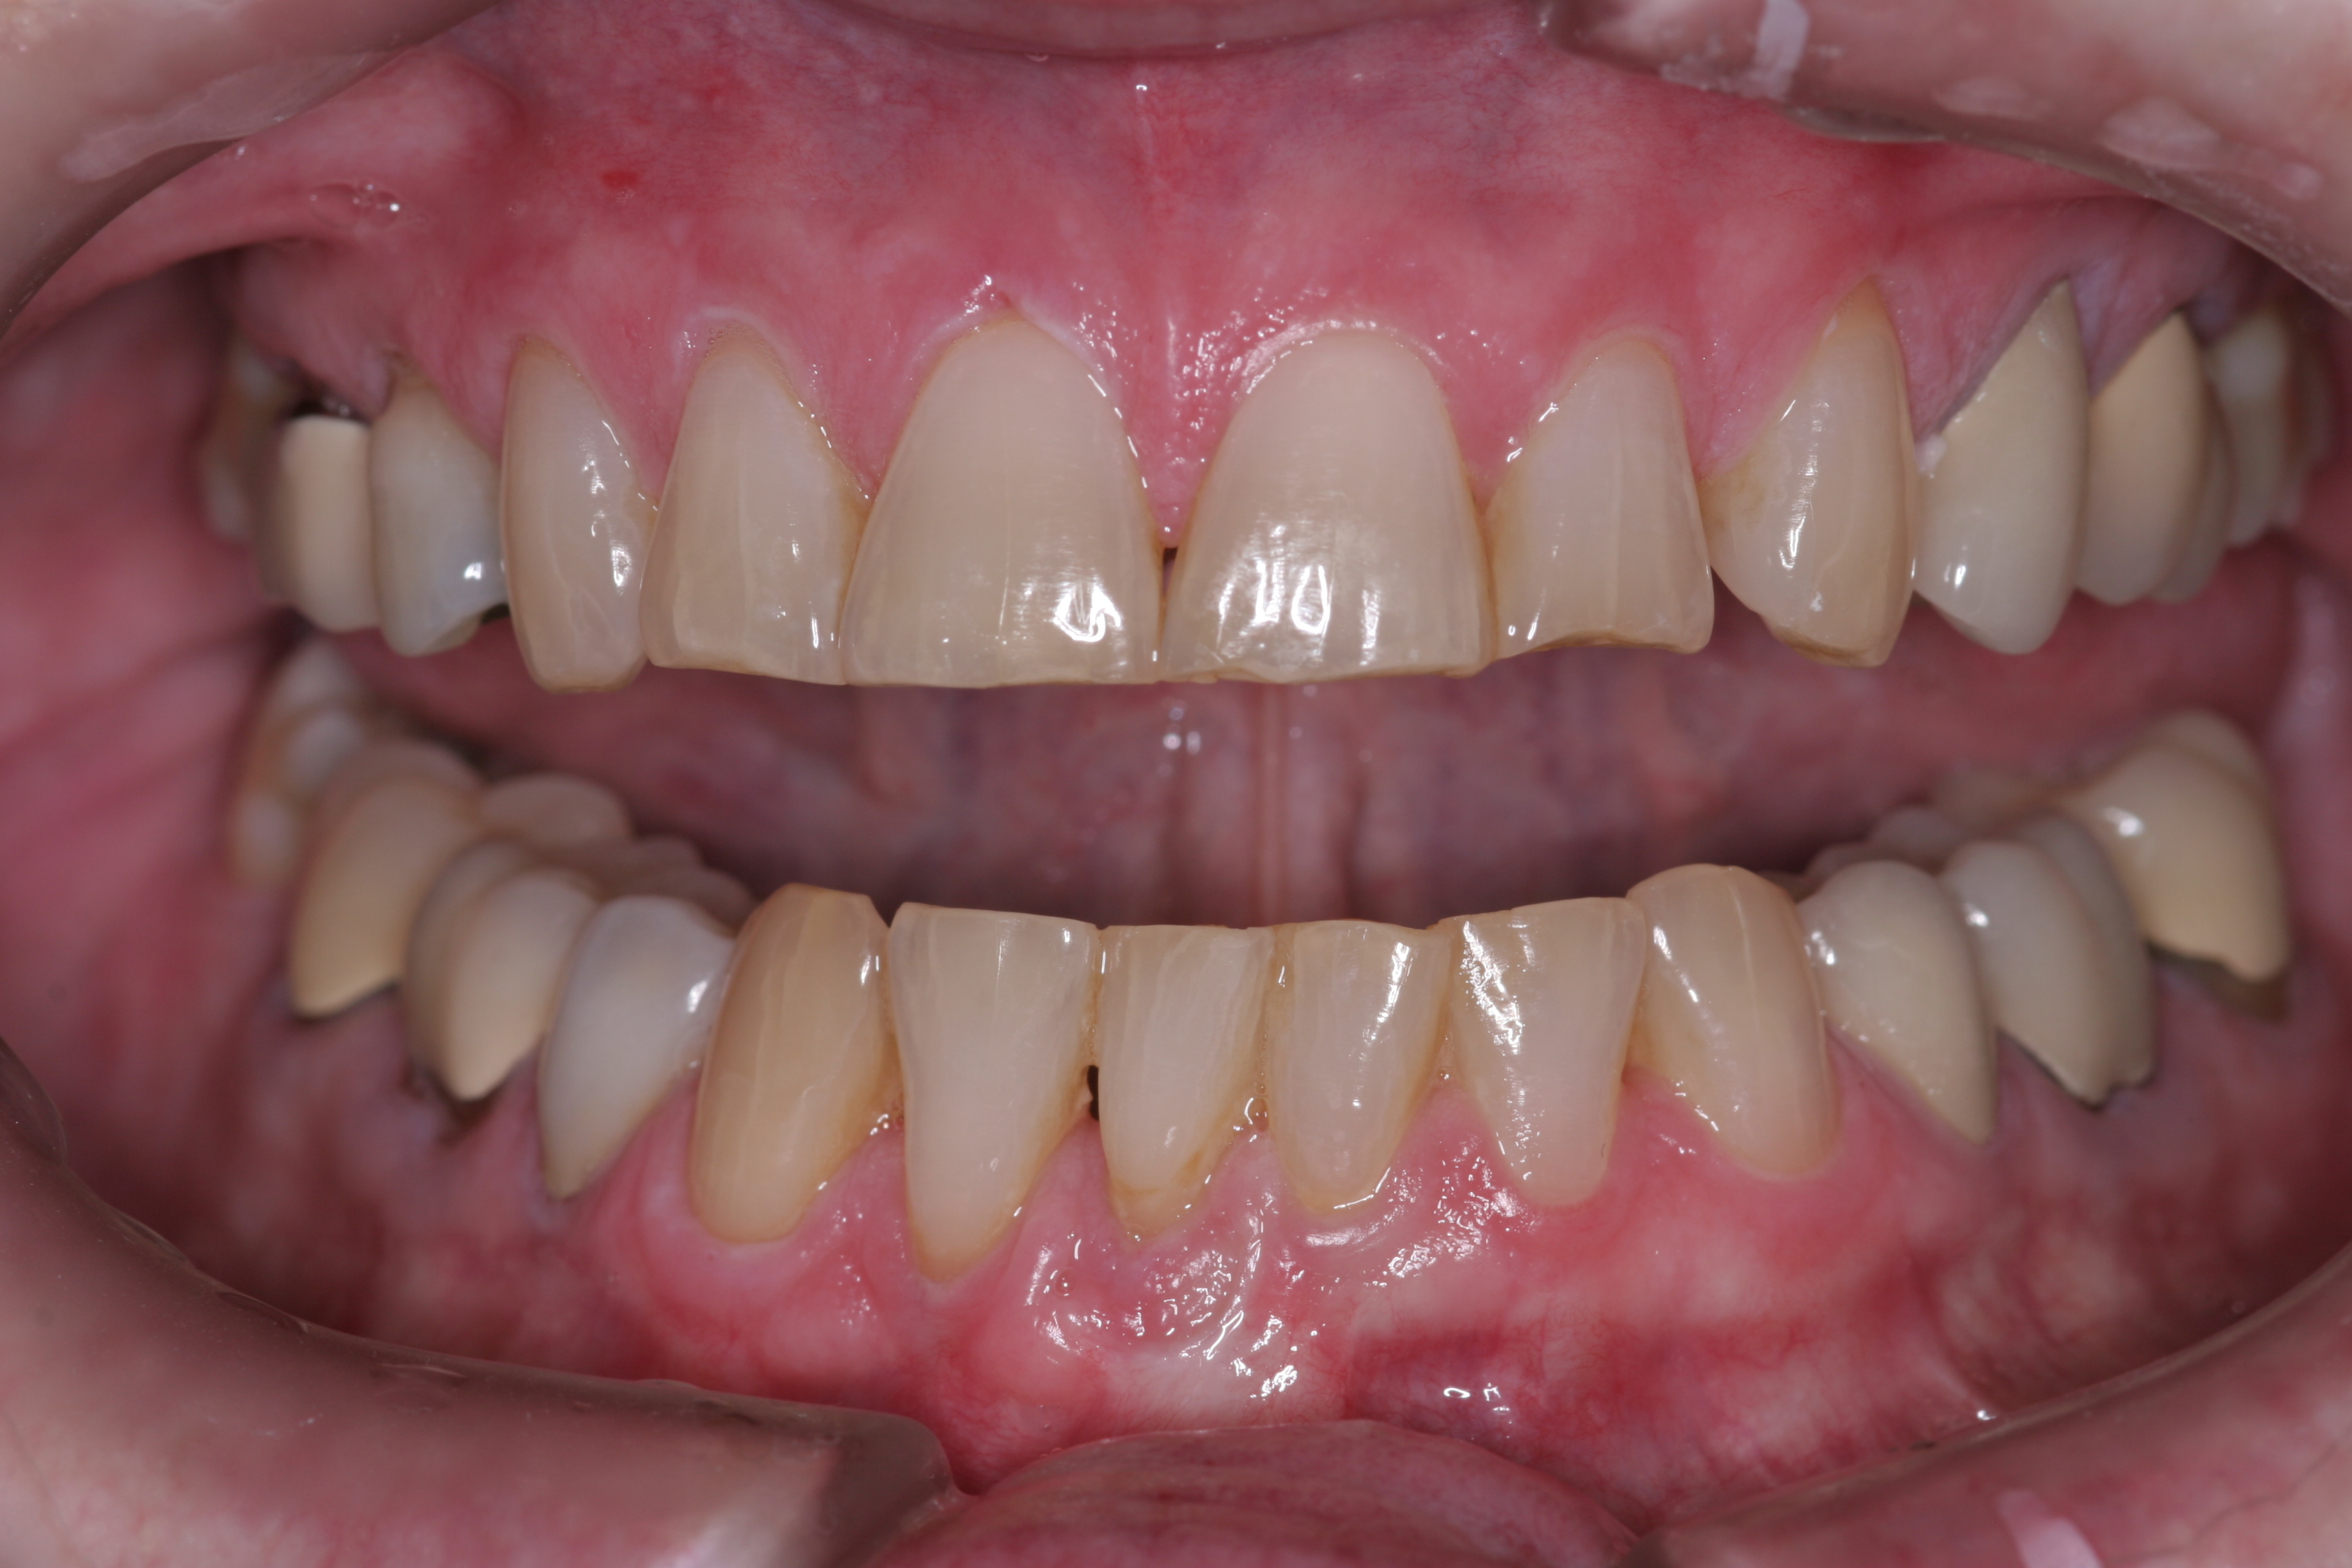

A patient presented with advanced generalized wear of her anterior teeth (Figure 10 and Figure 11). She was displeased with their overall appearance because of their color and wear (Figure 12). A complete examination was performed, revealing instability in her temporomandibular lateral poles bilaterally, sore muscles of mastication, advanced wear, a CR/MIP discrepancy, and loss of her anterior guidance due to the wear. Although the topic is beyond the scope of this article, the patient was also screened for possible sleep apnea. This included an evaluation of the Mallampati score, previous sleep therapy evaluation or treatment, snoring history, an evaluation of her neck size, her weight status, and the presence of the tonsils and their size. In every case, if this clinician suspects airway obstruction to be playing a role in tooth wear issues, the patient is referred to a sleep physician. The patient in this case displayed few apnea risk factors, and the patient’s anterior wear facets fit together like a “lock and key” pattern seen in parafunctional activity. Splint therapy was initiated to stabilize the joints and muscles. A repeatable CR position was verified through load testing. At this point diagnostic models, photographs, a CR bite record, and a facebow were taken and recorded.

(10.) A patient presented with advanced generalized wear of her anterior teeth, and was displeased with their overall appearance because of their color and wear.

Figure 10

(11.) A patient presented with advanced generalized wear of her anterior teeth, and was displeased with their overall appearance because of their color and wear.

Figure 11